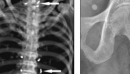

Американка 30 лет прожила с иглами в теле

Американка 30 лет прожила с иглами в теле 94-летняя женщина прожила 30 лет с иглами в позвоночнике и ногах, попавшими туда после сеанса иглоукалывания. В США пожилая женщина, страдающая от деменции, упала, пока не видели ее опекуны. В больнице врачи сделали рентген и выяснили, что кости пациентки в порядке, но их внимание привлекли странные пятна на... Далее>>